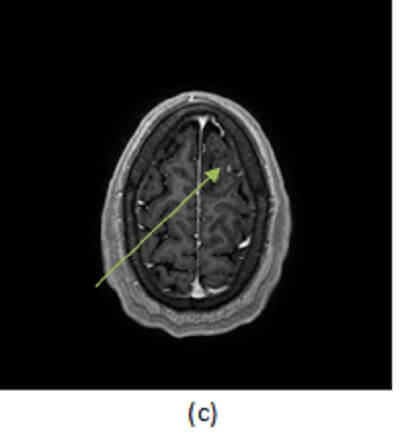

Figure 1: axial FLAIR (a, red arrow), DWI (b, blue arrow) and T1 post contrast (c ,green arrow) images of the brain reveal a circumscribed non restricting, non enhancing T2/FLAIR hyperintense mass in the high left frontal lobe.

Low grade astrocytomas are well differentiated intra-axial neoplasms. They typically present as circumscribed homogenous T2/FLAIR hyperintense supratentorial masses centered in the white matter without enhancement or restricted diffusion, although these tumors are infiltrating and microscopic disease is usually present beyond the margins apparent on imaging. There may be surrounding vasogenic edema and expansion of the cortex. Enhancement and necrosis are atypical and suggest progression to higher tumor grade such as anaplastic astrocytoma or glioblastoma multiforme.